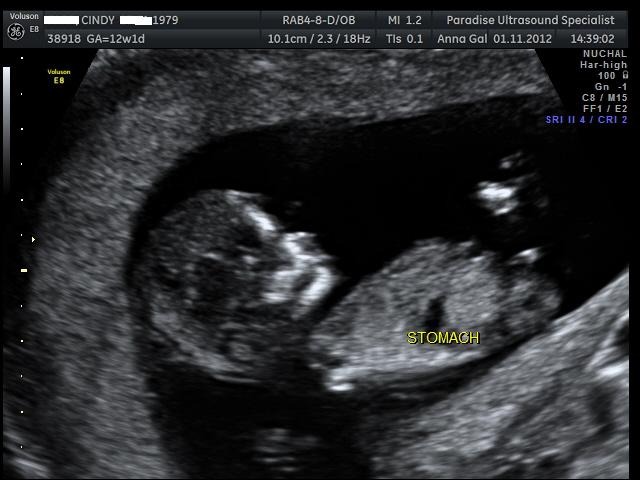

Here are the pics from my NT scan, the tech had a guess she said she is 70% positive the sex is.... can you guess? UPDATE - It's a boy :)